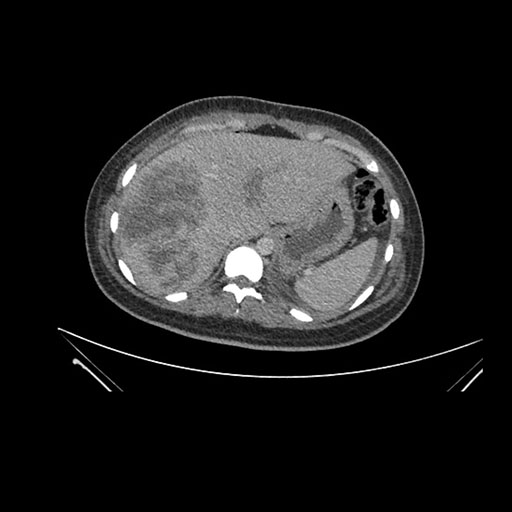

Imaging Analysis

Look through the patient's CT scan to identify any areas of concern for the necessary procedure.

Axial Arterial

Based on initial findings, which issue(s) would you be most concerned about?